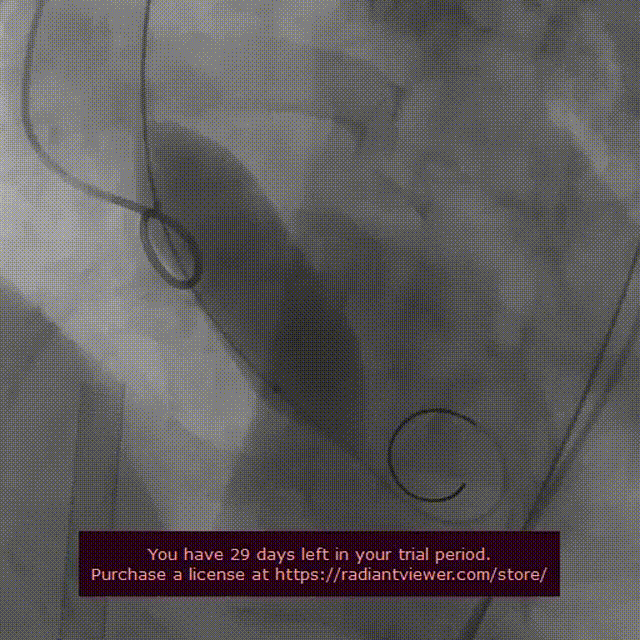

导丝跨瓣

第一次球囊预扩

第二次球囊预扩